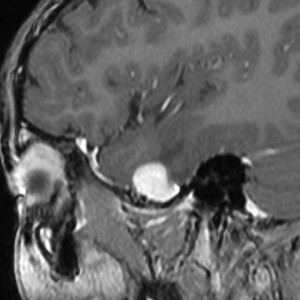

脳幹部から発生した退形成性神経節膠腫 grade 3

軽い右顔面神経麻痺で発症した小児で,右上下肢の軽度の失調症もありました。脳幹部(橋)の右背側から発生した腫瘍で,軽度の閉塞性水頭症を合併しています。左はT2強調画像で,橋の右側ににじむような浸潤像と浮腫があります。腫瘍は小嚢胞を形成してT2強調画像で実質は等信号です。真ん中の画像はCISS画像で橋が腫大しているのがよくわかります。右側はガドリニウム増強像で,全体が増強されてまだらな増強所見となっています。正中後頭下開頭で全摘出 gross total removal して,局所放射線治療とtemozolomide, cisplatine, etoposide, gleevec, hydoreaなどの化学療法を行いましたが,手術後4ヶ月で激しい播種再発を来しました。